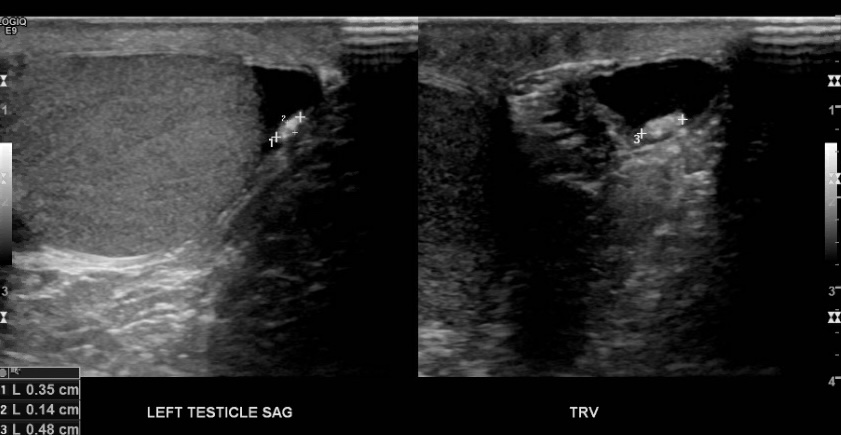

The appendix testis is a vestigial remnant of the Müllerian duct. It is a little nub of non functioning tissue that is normally located in the superior pole of the testicle. If this structure twists (torsion) it can lead to inflammation and pain. This process is most commonly seen in pediatrics especially prepubescent boys.

Clinically there will be pain, in some case epididymitis can develop. The normal appendage is not normally seen in routine scans, though it may reveal itself if there’s a hydrocele. There may also a “blue dot sign” which is a palpable, tender nodule that appears blue/purple under the skin on close inspection.

It is thought that once this tissue becomes necrotic it detaches from the tesis to be a freely moving object in the tunica vaginalis, it then undergoes calcification leading the o scrotal pearl (aka scrotolith).